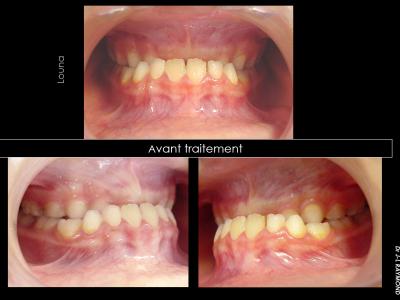

Les classes III par brachymaxillie (les plus fréquentes) sont associées à une bascule du plan d'occlusion maxillaire vers le haut et vers l'avant, identifiable à l'examen de la cinématique mandibulaire : les mouvements sont propulsifs en latéralité.

Leurs prises en charge en orthodontie systémique doivent corriger cette anomalie verticale en retrouvant une cinématique mandibulaire frontale.